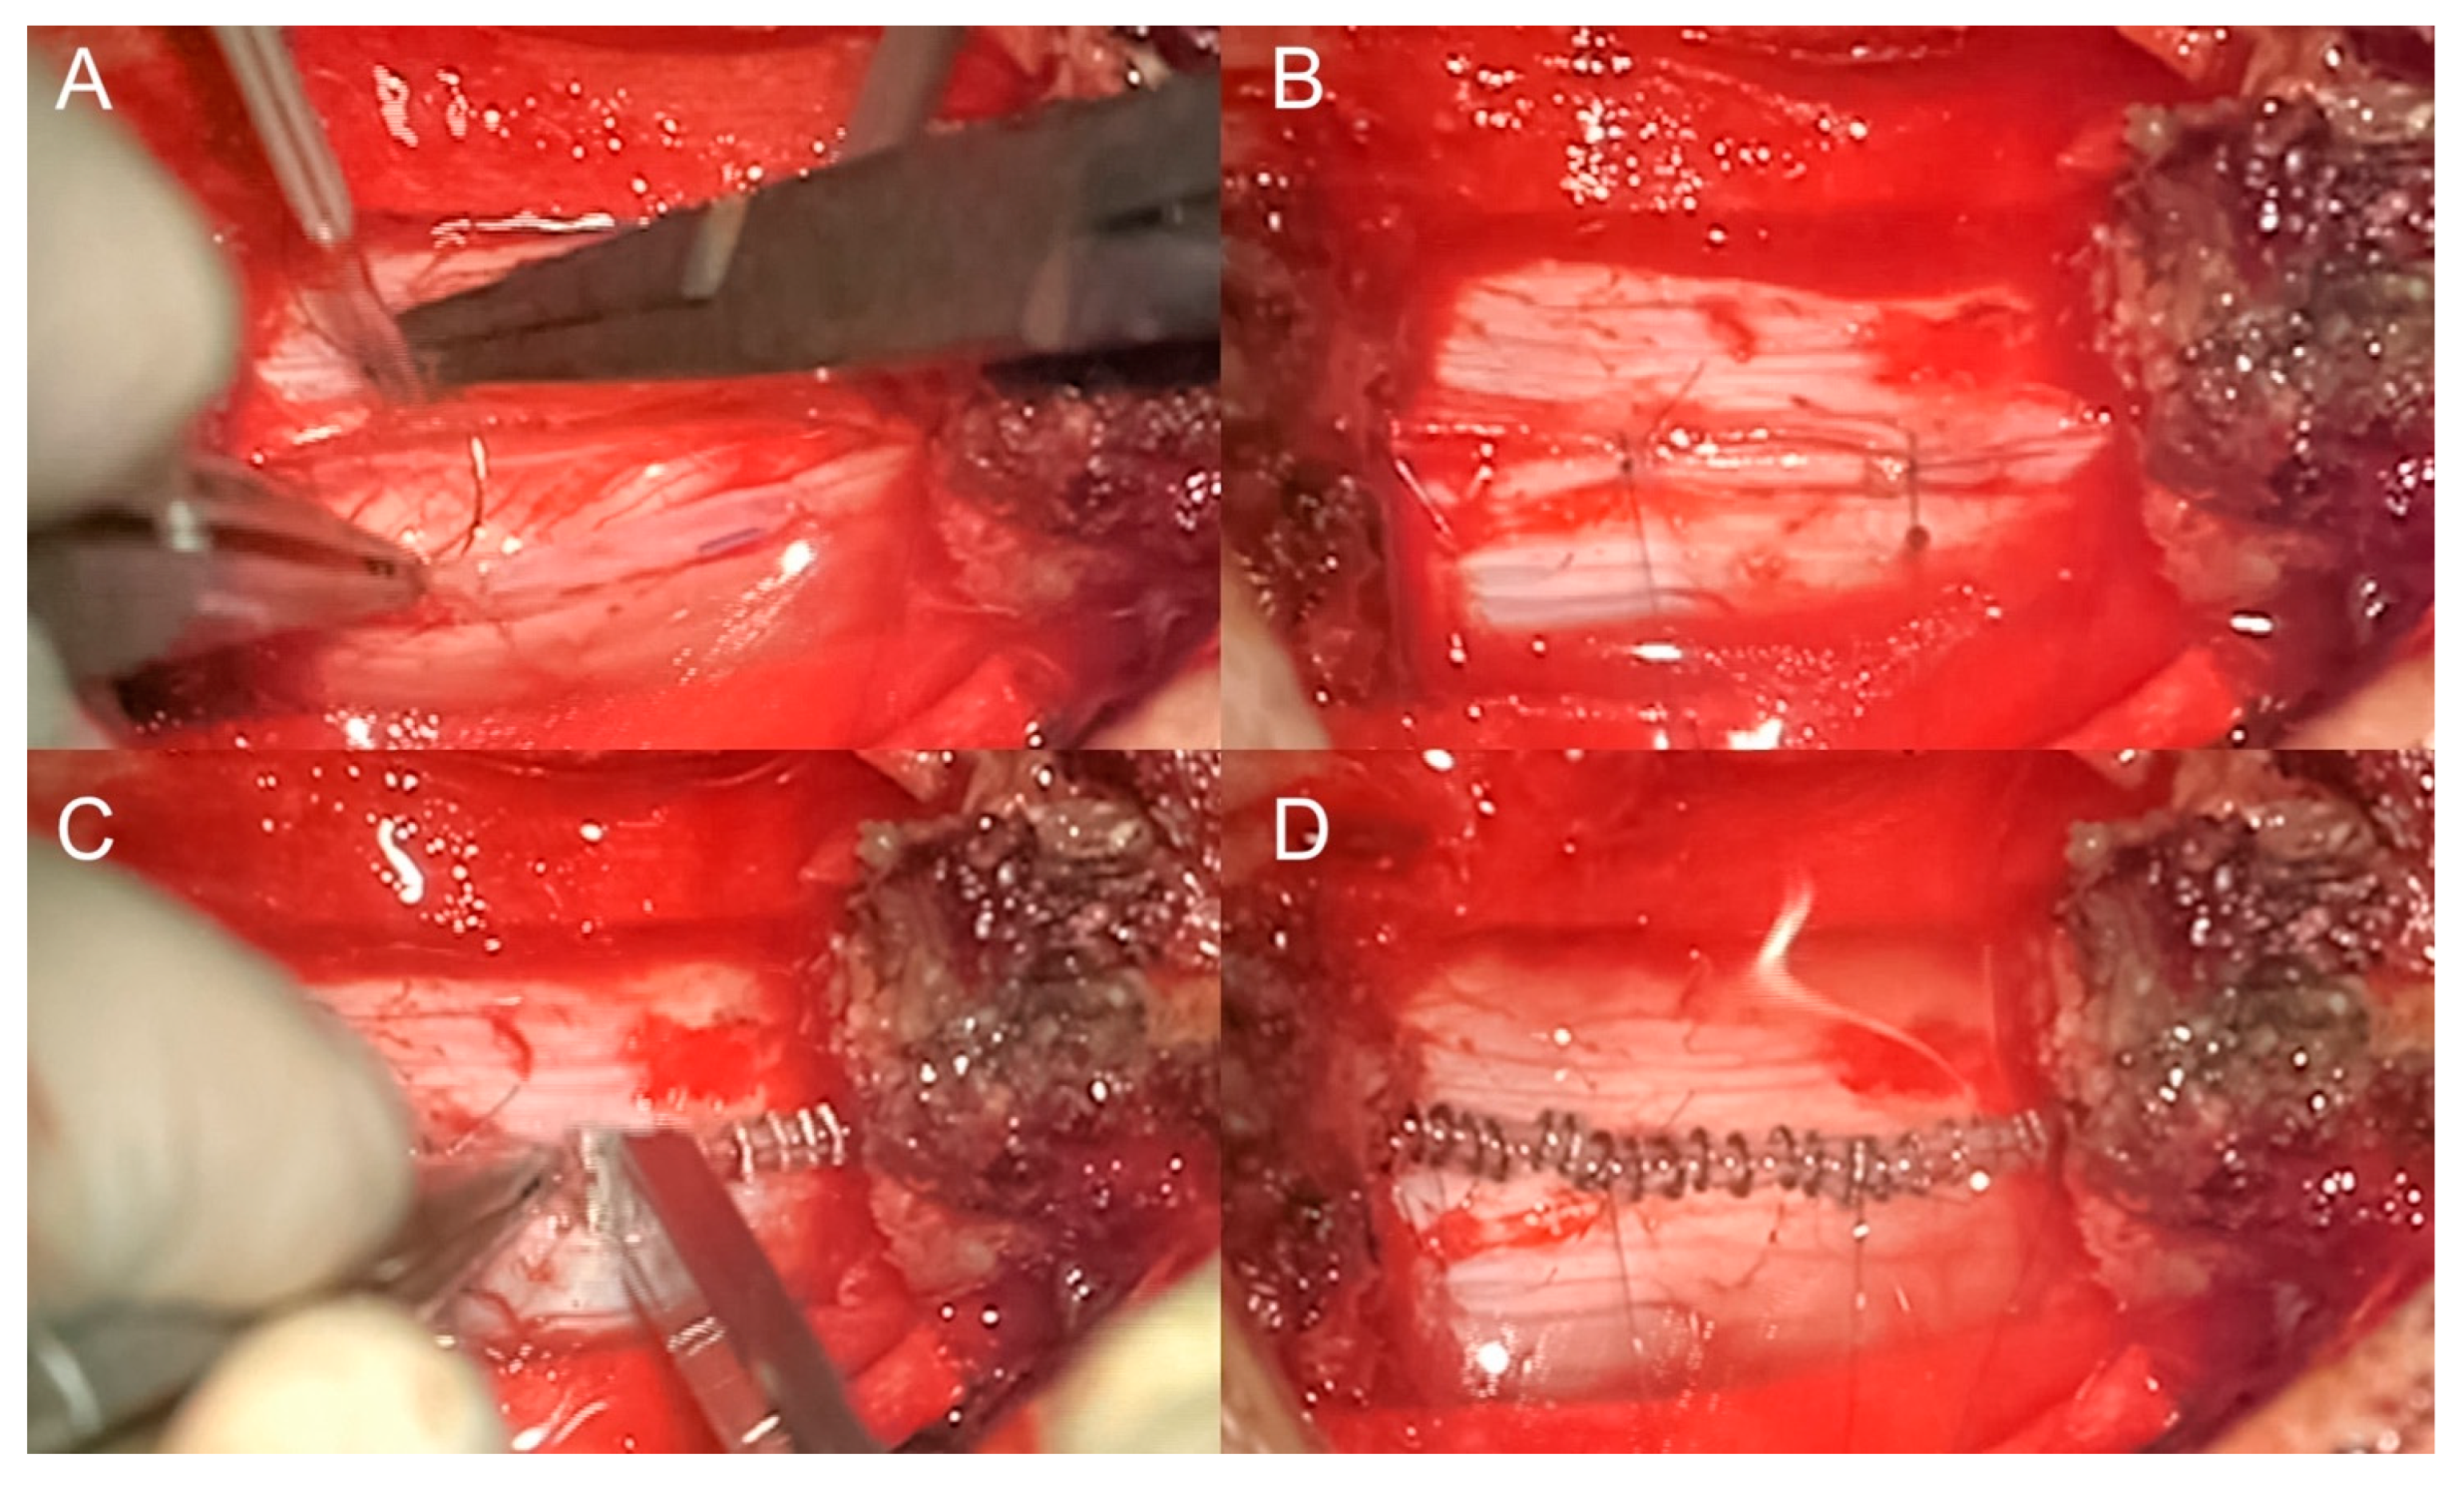

We prospectively analyzed a series of patients operated on at our Neurosurgery Department from August 2017 to December 2023 for resection of intradural spinal lesions both intra- and extramedullary. The study includes adult patients who underwent resection of intradural spinal tumors with an intact dura mater, where dural closure was achieved using non-penetrating titanium clips. Excluded from the study were patients with a history of prior surgery for intradural spinal lesions, those who experienced incidental durotomy requiring suturing, and patients whose postoperative dural defects necessitated the use of artificial dural patches. All patients underwent the same closure technique and postoperative cares protocol. In detail, dural closure was achieved by the placement of non-penetrating titanium clips (AnastoClip®) and sealant; patches (gelatin sponge or Tachoseal®) or autologous graft (adipose or muscular tissue) were applied in selected cases. Patients deemed at risk were kept in bed for 24 to 48 h, while the majority were mobilized the day after surgery. The surgical technique and postoperative cares protocol are shown in Figure 1 and detailed in Appendix A.

Closure technique for intentional durotomy. We use the Prolene 6-0 curved needle suture thread for suspension of dura mater during dural opening and to affix two to three stiches for the closure, as is described in previously published papers on the use of titanium clips (two at the extremities of dural opening and one or two eventual stiches in the middle depending on the dural opening size) [20,21]. This approach has the advantage that the needle has the same diameter as the thread. Subsequently, we apply titanium clips for dural closure using a specialized applicator, as is described in the technical note by P. Marks et al. and the experimental studies by K. Ito et al., followed by the application of a sealant to ensure a watertight closure [17,21]. At the end, we ask the anesthetist to perform a Valsalva maneuver to check eventual tears. Finally, we close the muscular plane with detached stiches and fascial plane with tight running suture or detached stiches. The subcutaneous and cutaneous plane is performed with suture and/or staples. Usually, we use subfascial hematic for draining expect in very small openings.

Figure 1. Closure technique for intentional durotomy. For the closure of the dura mater, we use two to three stitches with Prolene 6-0 suture thread and a curved needle: two stitches are placed at the edges of the dural opening, with one or two additional stitches in the middle, depending on the size of the opening (A,B). Titanium clips are then applied to secure the dural closure, followed by the application of a sealant (C,D).